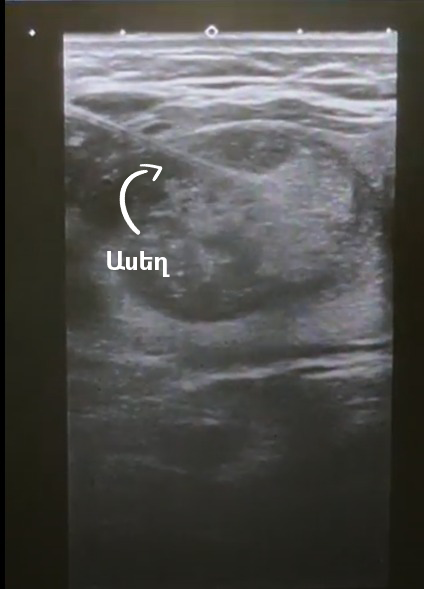

Биопсия — это минимально инвазивная процедура, выполняемая под ультразвуковым контролем и при бодрствующем пациенте. Сначала врач обрабатывает область шеи антисептиком, а затем наносит местный анестетик. С помощью ультразвукового устройства интервенционный радиолог локализует узел, чтобы ввести в него иглу. Он использует очень тонкую иглу, тоньше той, что используется для взятия крови из вены. Затем он попросит вас не двигаться, не разговаривать и не глотать во время введения иглы. После того как образец будет взят, он отправляется в лабораторию для дальнейшего исследования.